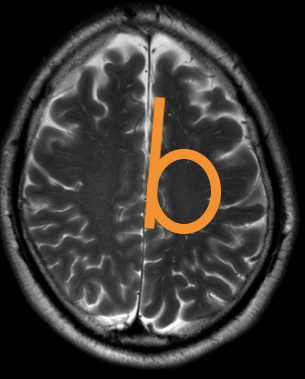

As a senior resident I reported an MRI of the brain of a patient with the cortex looking diffusely abnormal. There was a comparative scan, made 5 years earlier, briefly after the new 3T scanner had been set up in our hospital. This initial scan had been interpreted as normal by the professor in neuroradiology, a very knowledgeable doctor. Although the diffuse cortical abnormality was already visible, it was not recognised because inexperience with the 3T image.

Neuroradiology requires not only familiarity with the normal (MR) image but also understanding of the (patho)physiology. Whenever the physiology of the brain becomes too complicated for me, I go back in embryology to the neural tube, before the neurons and glial cells started to move and intertwine.

In Brain bit by bit vlogs I would like to share and show what I learned and know about different brain diseases, commenting on the radiological macroscopic picture and discussing what happened and happens at the microscopic, invisible cell level. Because this knowledge enables not only recognition of focal, obvious lesions in the brain but also diffuse, subtle disease that has just as much impact on life.